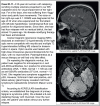

Results: In a cohort of 194 pSS patients, 22 patients had a CNS manifestation. In this CNS group, 19 patients had a lesion pattern suggestive of demyelination. While there were no obvious differences in the patients' epidemiological disposition or rate of other extraglandular manifestations, the CNS group differed from the remaining patients with pSS by having less glandular manifestations but a higher seroprevalence for anti-SSA/Ro antibodies. Notably, patients with CNS manifestations were often diagnosed with multiple sclerosis (MS) and treated as such, although age and disease course were atypical of MS. Many first-line MS agents were ineffective in these "MS look-alikes"; however, the disease course was benign with B-cell-depleting agents.

Conclusion: Neurological symptoms of pSS are common and clinically manifest mainly as myelitis or optic neuritis. Notably, in the CNS, the pSS phenotype can overlap with MS. The prevailing disease is crucial since it has a major impact on the long-term clinical outcome and the choice of disease-modifying agents. Although our observations neither confirm pSS as a more appropriate diagnosis nor rule out simple comorbidity, physicians should consider pSS in the extended diagnostic workup of CNS autoimmune diseases.